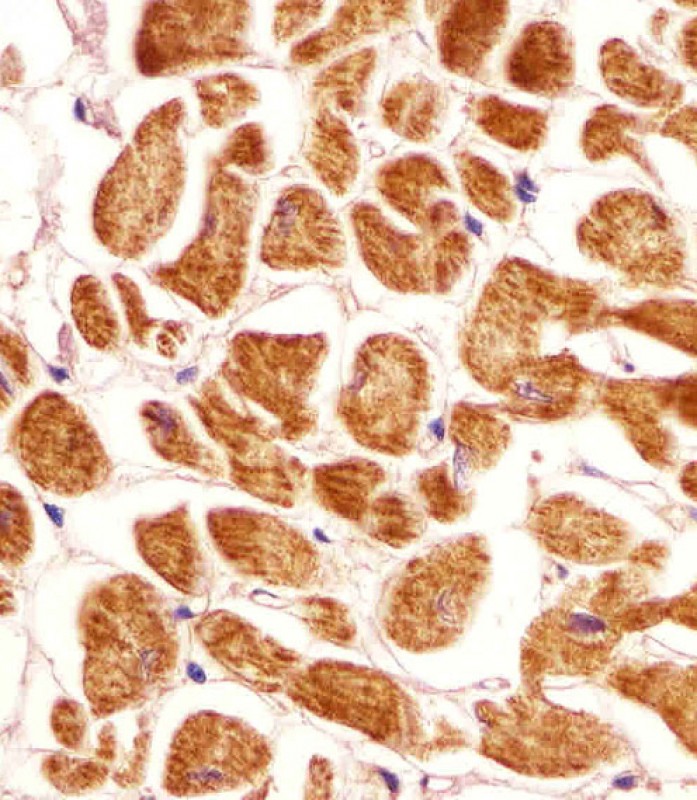

APR08965G staining PCCA in human heart tissue sections by Immunohistochemistry (IHC-P - paraformaldehyde-fixed, paraffin-embedded sections). Tissue was fixed with formaldehyde and blocked with 3% BSA for 0. 5 hour at room temperature; antigen retrieval was by heat mediation with a citrate buffer (pH6). Samples were incubated with primary antibody (1/25) for 1 hours at 37°C. A undiluted biotinylated goat polyvalent antibody was used as the secondary antibody.